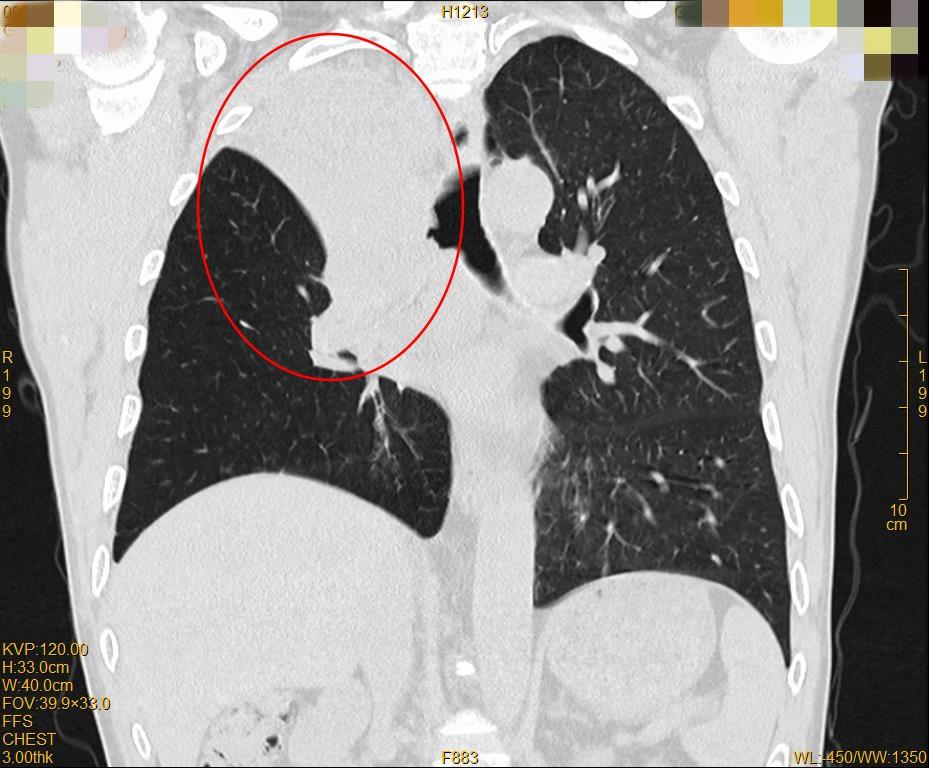

▲治疗前右肺上叶不张

▲治疗后肺复张